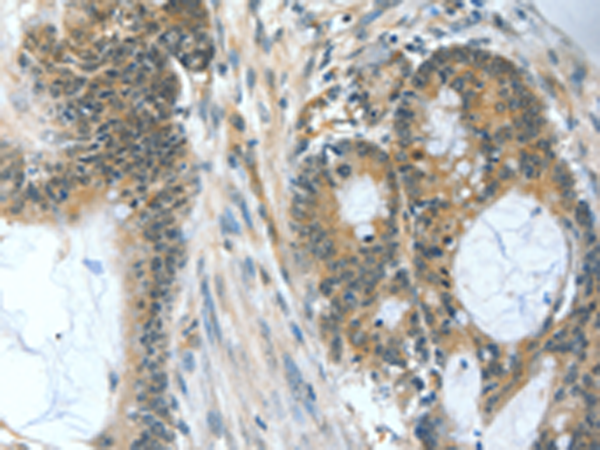

分类: 科研抗体货号: P06951别名: MEH; EPHX; EPOX; HYL1应用: IHC反应种属: Human, Mouse, Rat